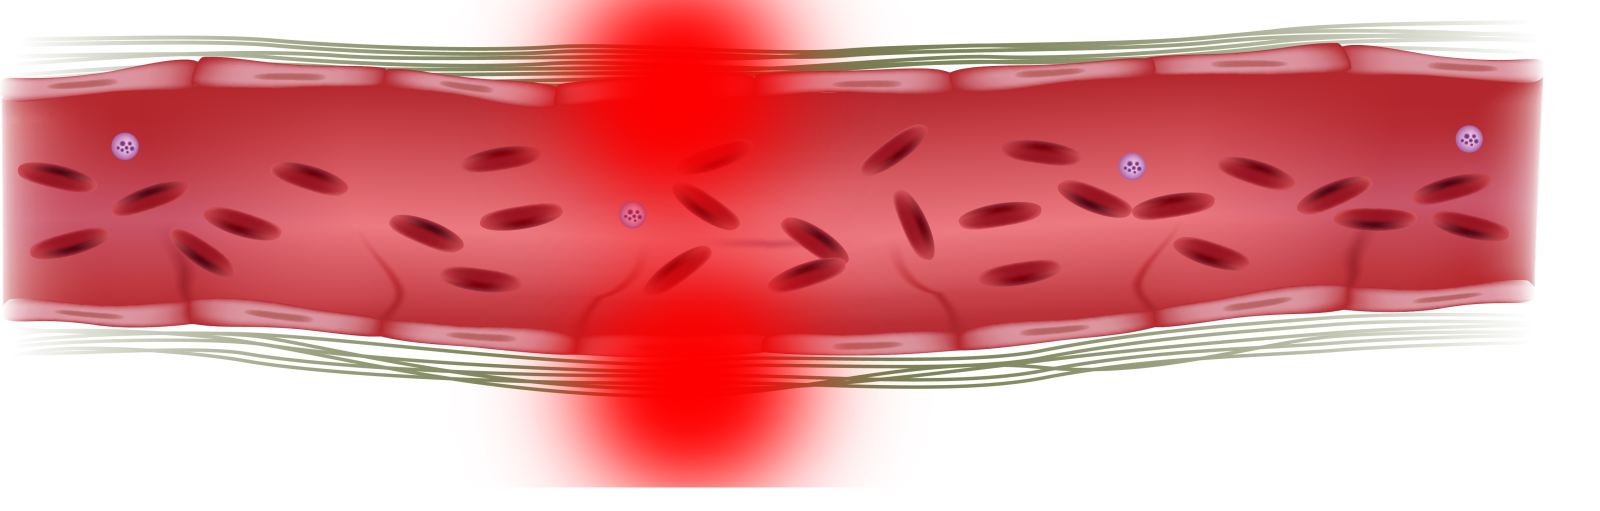

Воспаление стенок кровеносных сосудов

Воспаление стенок кровеносных сосудов возникает после первичного поражения русла кровеносного сосуда неизвестными причинами или инфекциями. Сопровождается заболевание аутоиммунным сбоем и отсутствием адекватной реакции организма на заболевание. Симптомы воспаления кровеносных сосудов разнообразные. Такая особенность связана с различной локализацией заболевания и возможностью поражения различных систем организма одновременно. К общим симптомам относят: поражение стенок сосуда, сильный зуд в пораженной области, снижение чувствительности кожного покрова, образование кожных кровоподтеков, мышечная слабость, красные пятна на кожном покрове, нарушение работы желудочно-кишечного тракта, отеки ног, головные боли.

Воспаление стенок кровеносного сосуда разделяют на несколько групп: воспаление стенок вены (флебит), воспаление капилляров (капиллярит), повреждение мелких артерий (артериалит), воспаление стенок больших артерий (артериит). Каждый вид воспалительного процесса сосудов характеризуется собственной симптоматикой и требует качественного лечения. Пред назначением лечения проводиться диагностика заболевания. Диагностика воспалительного процесса сосудов проводиться с помощью ультразвука и лабораторных тестов крови.